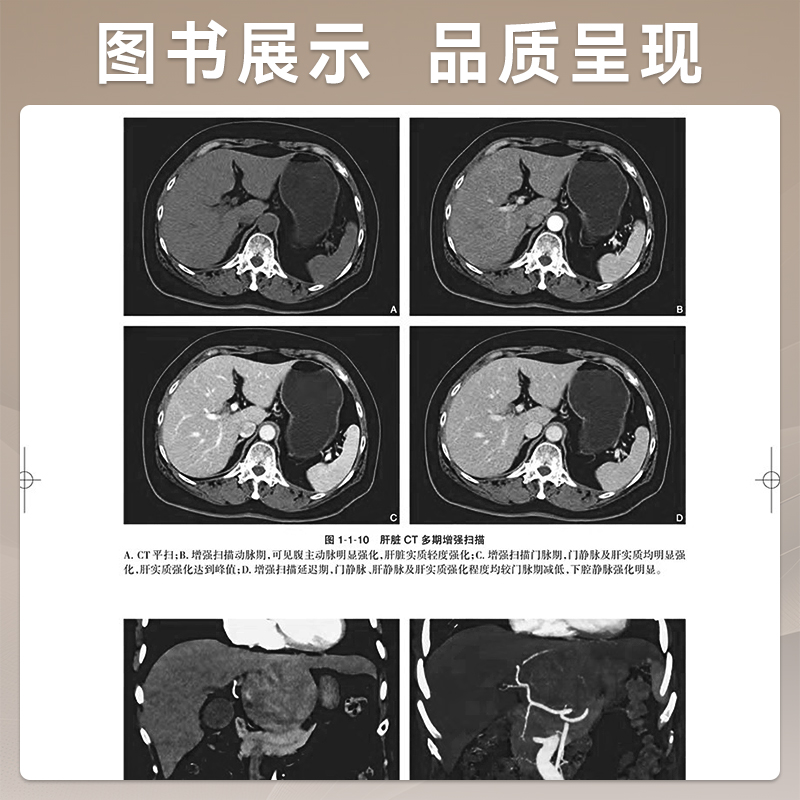

消化分册 人民卫生出版 严福华 临床阅片诊断胃肠道生理病理学 社9787117370745 肝胆胰脾器官临床影像学征象 中华影像鉴别诊断学